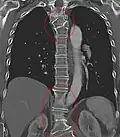

Several congenital block vertebrae in the transition from the thoracic to the lumbar spine and hemivertebrae. -

Congenital block vertebra in the lumbar spine (partial vertebrae 3 and 4). The rear portion of the disc still exists. -

Congenital block vertebra of the lumbar spine. CT volume rendering. -

Congenital block vertebra of the lumbar spine. CT volume rendering.